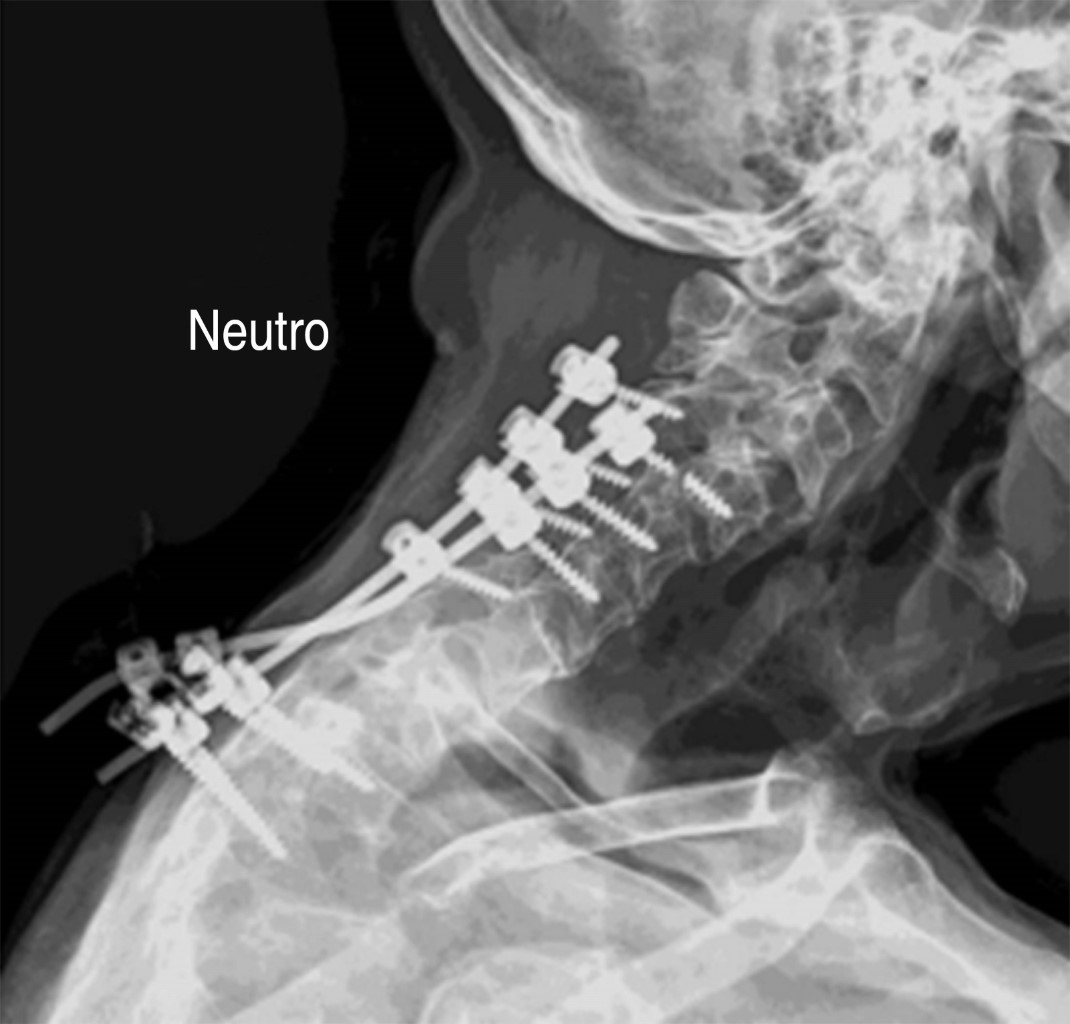

Se admitió hombre de 59 años de edad con diagnóstico de neurofibromatosis tipo 2 para tratamiento quirúrgico de deformidad iatrogénica de la columna cervical, consecuencia de un tratamiento previo realizado en otro servicio (Figura 1). A la admisión, el paciente presentaba una deformidad cifótica de la columna cervical con fallo del sistema de fijación utilizado, con exposición del material de fijación y signos de infección en el sitio operado.

Se propuso la tracción con halo gravitacional para la corrección gradual de la deformidad y se instaló el halo craneal en la primera etapa del tratamiento quirúrgico junto con la instalación de los nuevos implantes, desbridamiento y retirada de los implantes expuestos (Figura 2).